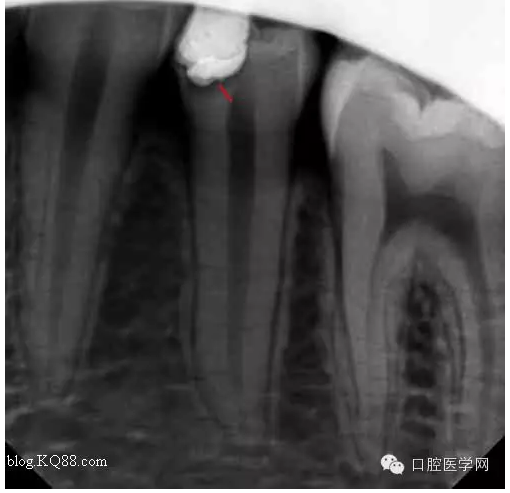

一月后復(fù)查:高聳的髓角變鈍,形成約0.5mm修復(fù)性牙本質(zhì)?;佳罒o癥狀。牙髓活力測試同對照牙。

兩月后復(fù)查:高聳的髓角變的更鈍。遠中髓壁形成較厚的修復(fù)性牙本質(zhì)。溫度測試同對照牙。